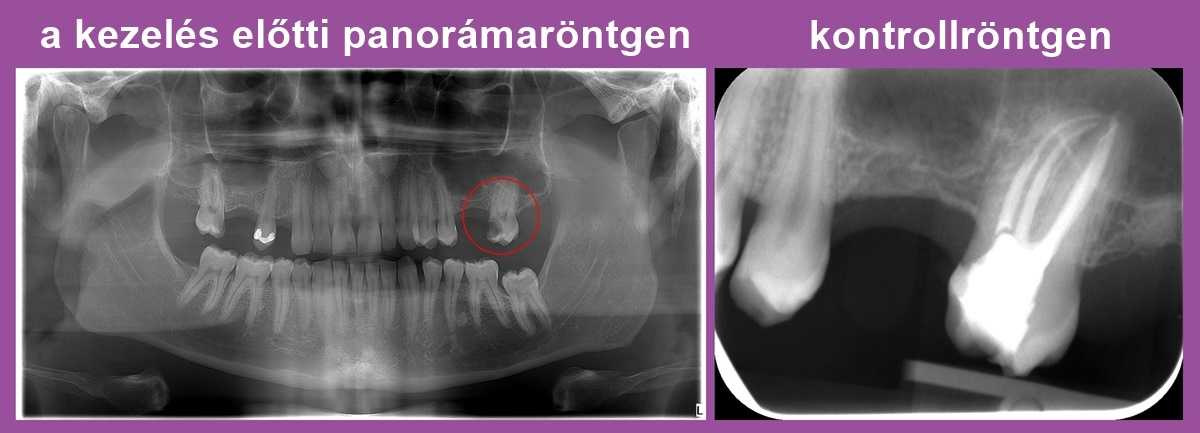

Dr. Molnár Katalin páciense arra panaszkodott, hogy foga érzékeny a hidegre és a melegre. Az első képen, a panorámafelvételen bekarikáztuk a fájdalmat kiváltó bal felső hetes fogat. Egy mély szuvasodás látható rajta, amely nagy kiterjedésű foganyag-veszteséget okozott. Nyilvánvalóvá vált, hogy az érzékenység hátterében ez a károsodás áll.

A fog megmentéséhez gyökérkezelés szükséges. Ám a röntgenfelvétel azt mutatja, hogy ennek a bal felső 7-es fognak – mint általában – 3 db foggyökere van (két külső az arc és egy belső a szájpadlás felé), ám az első-külső (ún. mesio-buccalis) foggyökérben 2 db gyökércsatorna is található.

A kontroll röntgenfelvételen jól kivehető, hogy a fognak elöl nem egy, hanem két gyökere van: ha ezt nem sikerül megtalálnunk és letömnünk, az később panaszokat és gócos tüneteket okozhat.